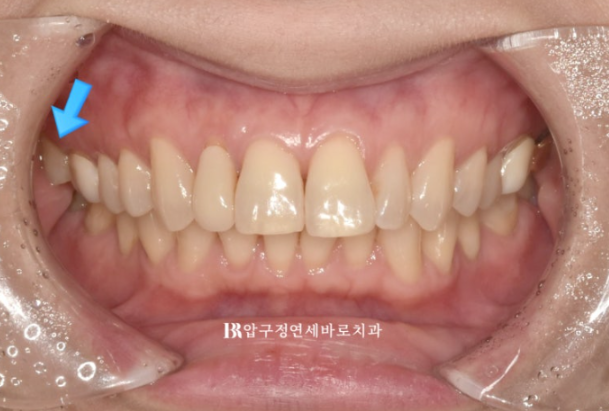

파란화살표 맨 뒤 큰어금니는 위 아래가 엇갈려 물리는 가위교합 입니다.

24.02

혀쪽으로 쓰러진 두번째 큰 어금니가 보입니다.

이 때문에 대합치인 위 두번째 큰 어금니와 제대로 교합이 안 되어서 가위교합 상태입니다.

이렇게 엇갈려서 교합이 안되는 상태를 가위교합 이라고 합니다.

앞니 배열 개선과 가위교합 개선

쓰러진 큰 어금니는 잘 세웠습니다.